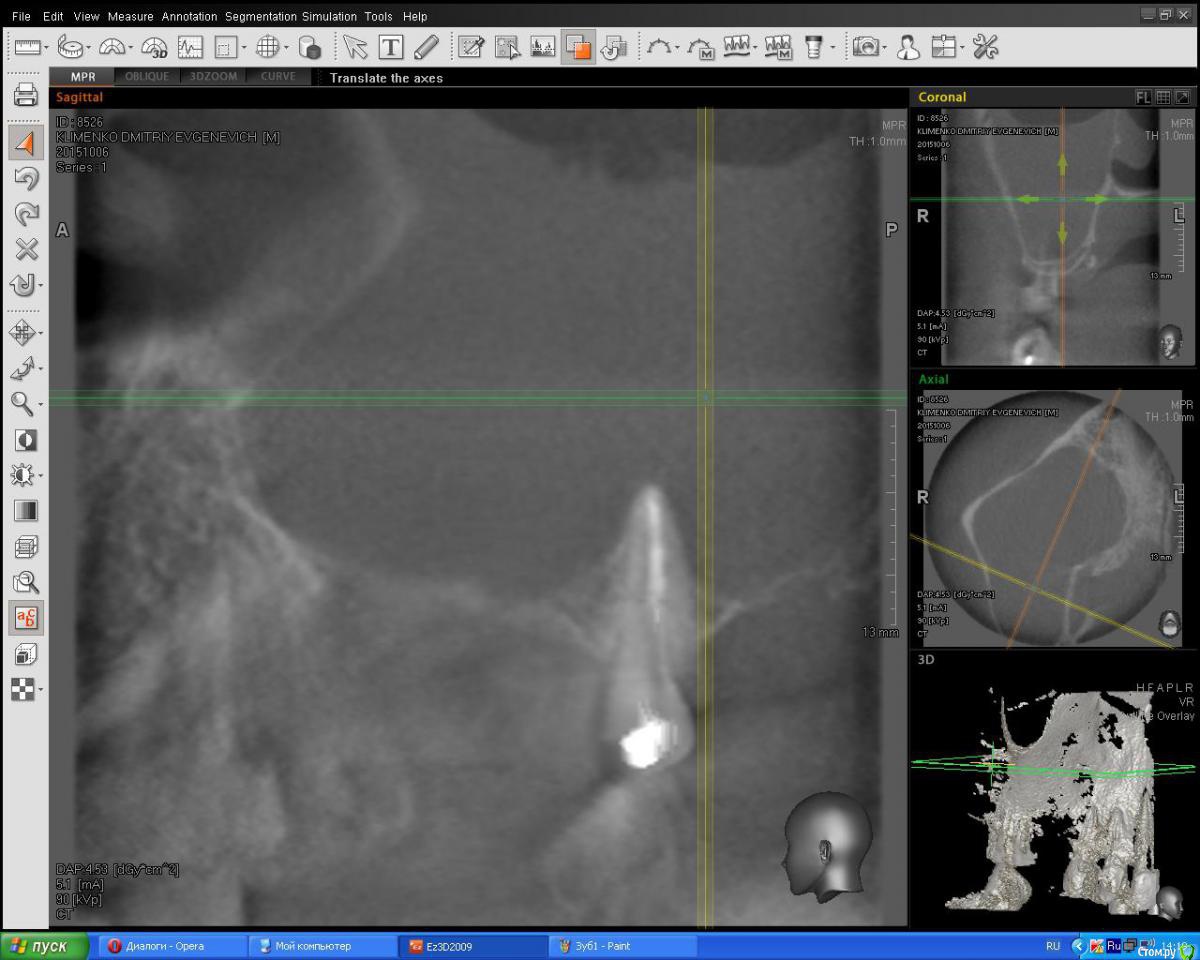

listopad19531 Опубликовано 11 октября, 2015 Поделиться Опубликовано 11 октября, 2015 Здравствуйте. Две недели назад мне перепломбировали каналы верхнего зуба (1-7, 7й справа). Ранее в зубе стояли штифты. Зуб начали готовить под коронку, штифты убрали и решили, что каналы лучше перелечить. После перепломбировки начался гайморит, сопровождаемый температурой 37,2, болями в виске и правом глазу, иногда боли отдаются в зуб. Антибиотики и лечение гайморита я провожу, но боли и температура остаются (это тянется 2 недели). Стоматолог говорит, что лечение выполнено качественно. ЛОР лечит гайморит и отправляет к стоматологу. И так далее... Выкладываю снимки. Вопрос. все ли в порядке с косточкой гайморовой пазухи? Не повреждена ли она? Продолжать ли лечить гайморит или перелечивать зуб? Возможно ли его теперь перелечить? Спасибо Ссылка на комментарий